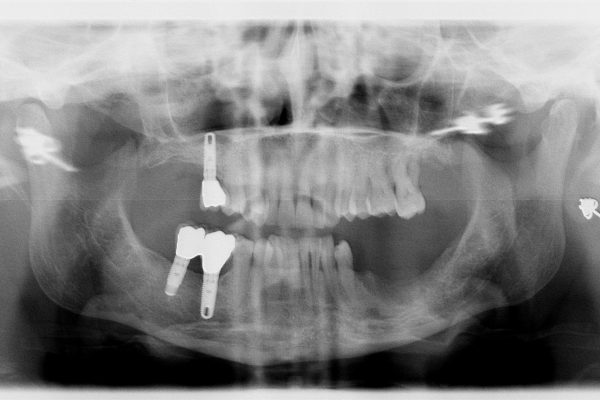

Il caso Clinico:

Importante perdita ossea Verticale ed orizzontale provocata dalla perdita di Impianti posizionati a causa della MANCANZA di una attenta diagnosi, piano di trattamento e capacità operativa, che avrebbero mostrato l’impossibilita di posizionare gli Impianti senza ripristinare lo spessore osseo adeguato …